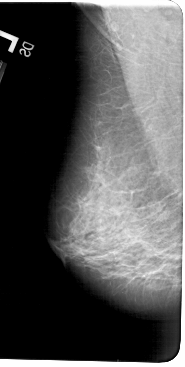

A_1602_1.RIGHT_CC

RIGHT_CC LINES 5446 PIXELS_PER_LINE 2941 BITS_PER_PIXEL 12 RESOLUTION 43.5 OVERLAY